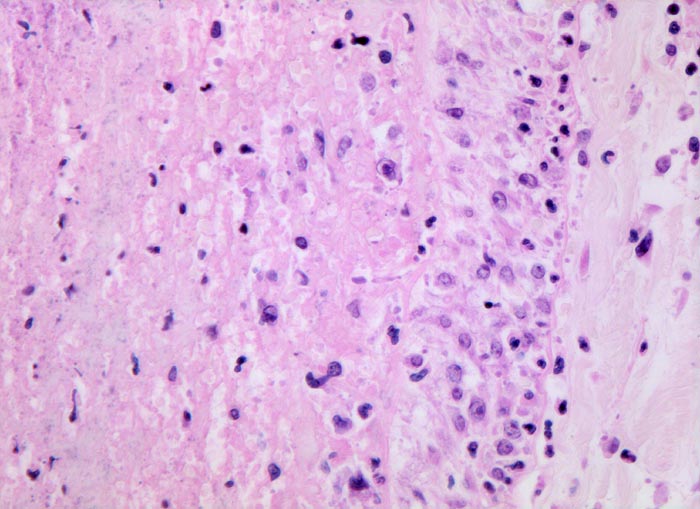

Morphologische Merkmale:

- Scharf begrenzte dreiecksförmige hämorrhagische Nekrose des Lungenparenchyms.

- Alveolen gefüllt mit zerfallenden Erythrozyten, Kerntrümmern und Fibrin.

- Lungengerüst erhalten im Randbereich der Nekrose, nicht mehr erkennbar im Zentrum.

- Abgeblasste Zellkerne in der Nekrosezone.

- Pulmonalarterienast mit nicht wandhaftendem Thrombembolus am Rand des Infarktes.